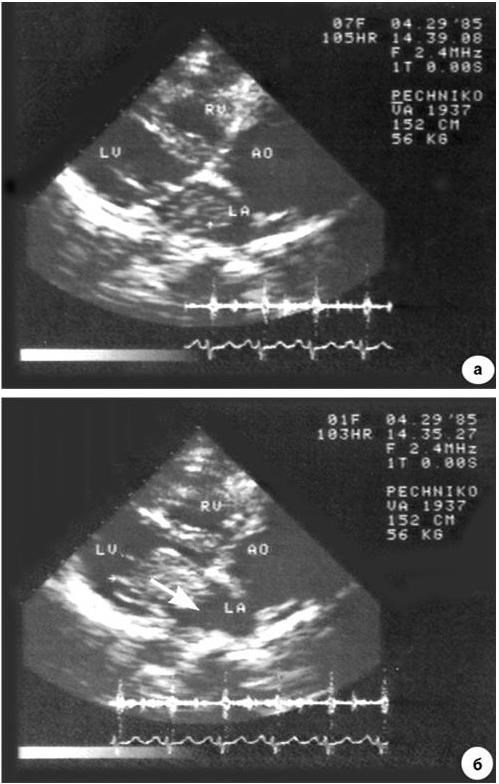

Рис. 1.12. Эхокардиограмма больного с миксомой левого предсердия.

Во время систолы левого желудочка (а) опухоль локализована в левом предсердии, во время диастолы (б) она пролабирует в полость левого желудочка (миксома указана стрелкой)

Размеры сердца при рентгенологическом исследовании обычно не изменены. При ЭКГ-исследовании также отсутствуют специфические изменения. Основной метод диагностики – эхокардиография, выявляющая эхопозитивное образование в месте локализации опухоли (рис. 1.12). Опухоль визуализируется также при компьютерной томографии, радиоизотопной вентрикулографии. Ангиография не рекомендуется из-за возможности повреждения рыхлой опухоли (эмболии).